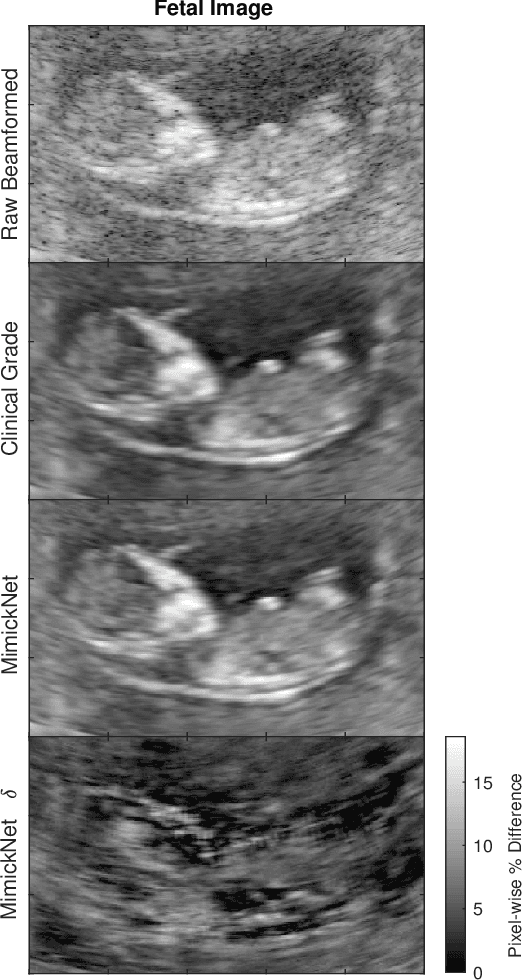

Abstract:Image post-processing is used in clinical-grade ultrasound scanners to improve image quality (e.g., reduce speckle noise and enhance contrast). These post-processing techniques vary across manufacturers and are generally kept proprietary, which presents a challenge for researchers looking to match current clinical-grade workflows. We introduce a deep learning framework, MimickNet, that transforms raw conventional delay-and-summed (DAS) beams into the approximate post-processed images found on clinical-grade scanners. Training MimickNet only requires post-processed image samples from a scanner of interest without the need for explicit pairing to raw DAS data. This flexibility allows it to hypothetically approximate any manufacturer's post-processing without access to the pre-processed data. MimickNet generates images with an average similarity index measurement (SSIM) of 0.930$\pm$0.0892 on a 300 cineloop test set, and it generalizes to cardiac cineloops outside of our train-test distribution achieving an SSIM of 0.967$\pm$0.002. We also explore the theoretical SSIM achievable by evaluating MimickNet performance when trained under gray-box constraints (i.e., when both pre-processed and post-processed images are available). To our knowledge, this is the first work to establish deep learning models that closely approximate current clinical-grade ultrasound post-processing under realistic black-box constraints where before and after post-processing data is unavailable. MimickNet serves as a clinical post-processing baseline for future works in ultrasound image formation to compare against. To this end, we have made the MimickNet software open source.